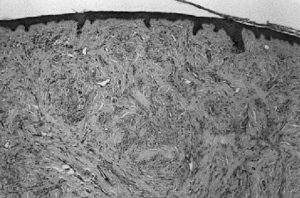

Se procedió a su extirpación quirúrgica y estudio histo-patológico el cual mostró a nivel de dermis papilar y reticular células névicas agrupadas en tecas en planos superficiales y en fascículos elongados hacia la profundidad, estando en ambas regiones rodeadas por gruesos haces colágenos esclerosos (Fig. 2). Se observaban, además, telangiectasias en los capilares superficiales y discreto infiltrado inflamatorio mononuclear perivascular.

FIG. 2.--Células névicas en tecas superficiales y fascículos profundos rodeadas por gruesos haces colágenos esclerosos (H-E).